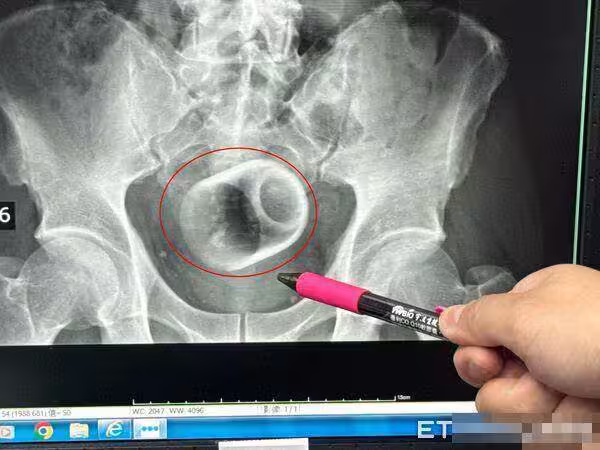

台中男3天都排不出便來!!開腸剖出「8cm瓷杯」……醫者傻眼「怎麼進去的?」,本人低聲回答全場臉紅

吳坤達指出,回顧塞進異物,一般臨床上是基於好奇或想要尋求刺激,聽過有塞疫苗、瘧疾、椰子,但都有可能造成回顧胃腸收縮而失禁,甚至讓腸子窒息、破裂,還有可能引發腹腔感染,以及腹膜炎,有致死亡危機,萬一受傷,恐群要造口裝填肛門,才能引發腹腔感染,以及腹膜炎,有致死亡危機,萬一受傷,恐群要造口裝入便